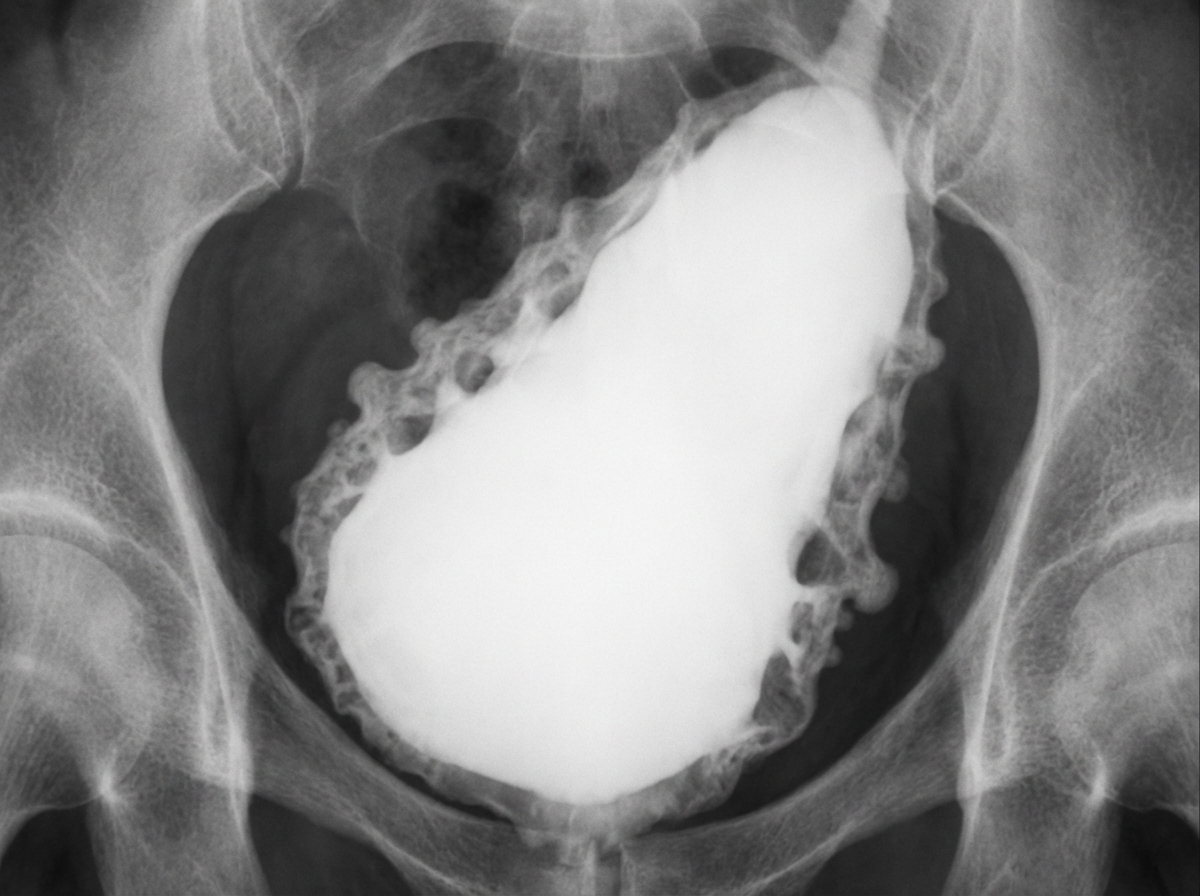

A given cystogram appearance is a characteristic feature of which of the following conditions?

Explanation: ***Neurogenic bladder*** - Shows characteristic **"Christmas tree"** or **trabeculated appearance** on cystography due to detrusor muscle hypertrophy and irregular bladder wall thickening. - Results from **neurological disorders** affecting bladder innervation, leading to incomplete emptying and compensatory muscle changes. *Congenital anomalies of the genitourinary tract* - Cystographic findings are highly **variable** depending on the specific anomaly (duplications, diverticula, etc.). - Do not produce the characteristic **trabeculated pattern** seen in neurogenic bladder dysfunction. *Tuberculosis* - Produces a **"thimble bladder"** appearance with severe contracture and reduced capacity on cystography. - Shows **irregular, contracted bladder walls** with calcifications, distinct from the Christmas tree pattern. *Schistosomiasis* - Causes **calcified, contracted bladder** with "eggshell calcification" visible on plain radiographs. - Results in **reduced bladder capacity** and smooth wall thickening, not the trabeculated Christmas tree appearance.